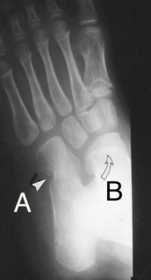

| What is shown by A and B? | A = Talonavicular coalition B = Calcaneocuboid coalition |